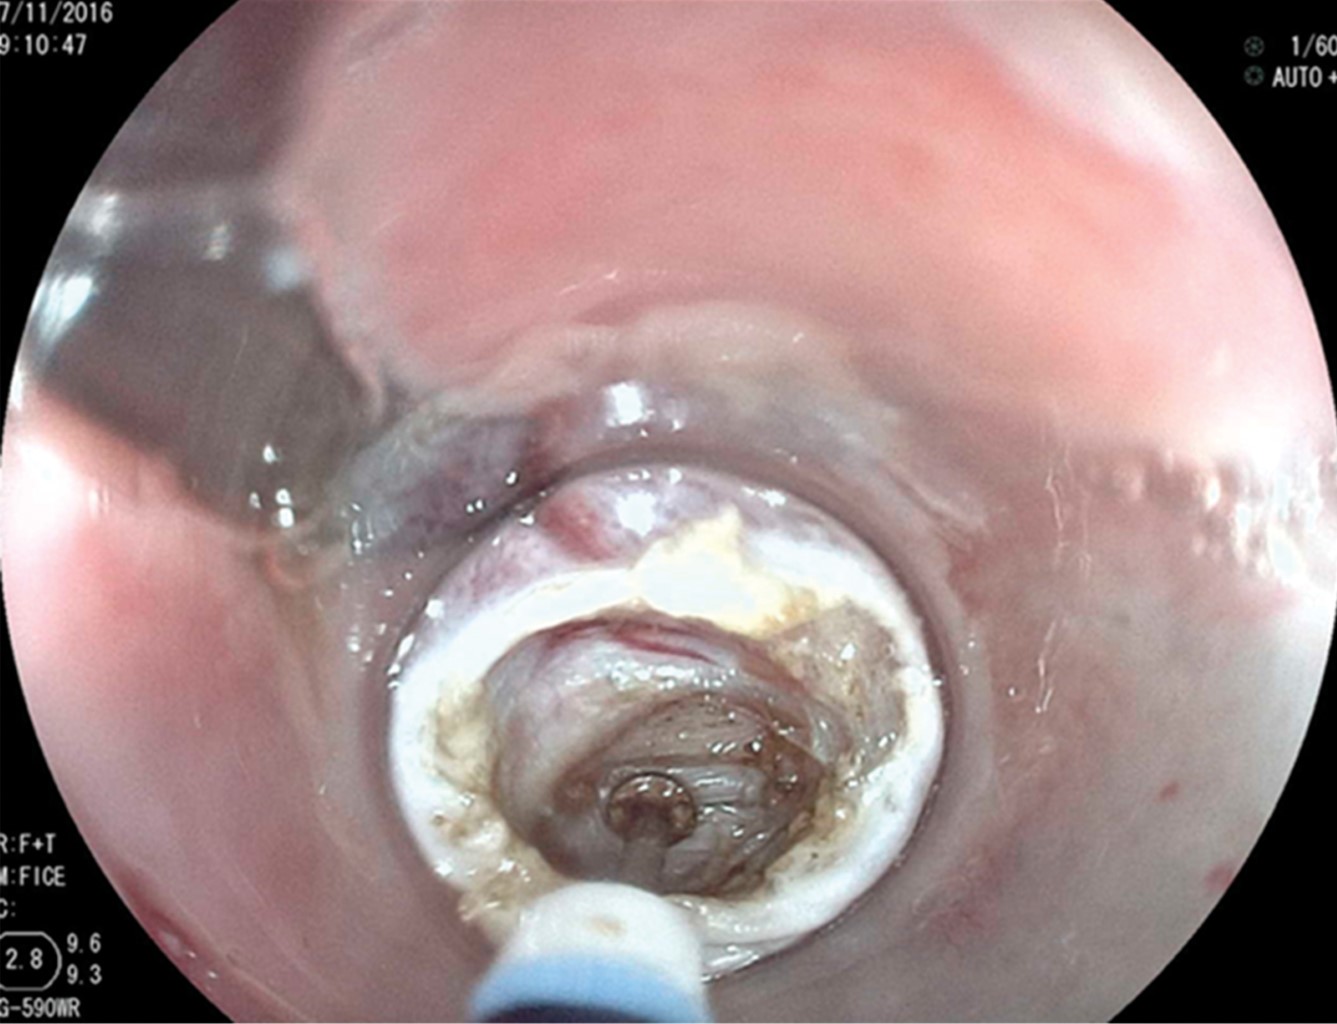

In the first 10 patients, once the esophageal lumen is identified, a metal guide is introduced and over it, a 7 mm or 21 Fr Savary-Gilliard dilator, which reaches the stomach and is left there. This adequately delimits the light of the diverticulum and esophagus (Figure 2). A clear plastic cap (MBL 6-1 Cook Endoscopy™) is placed at the distal end of the endoscope insertion tube and used as a spacer, which allows identification of the cricopharyngeal muscle septum. In the first 10 cases, an Olympus™ video gastroscope model GIF-H140 with an Olympus™ CV-140 image processor (Olympus Optical Co., Tokyo, Japan) of 9.8 mm diameter were used. Also, an Olympus UES-40 SurgMaster™ electrosurgical unit, and a needle knife (Needle Knife™, Cook Endoscopy, Winston-Salem, NC), were used. A cut was made in the edge of the esophageal light in the middle of the septum and towards the light of the diverticulum. First, the mucosa was cut exposing the cricopharyngeal muscle fibers (Figure 3). The cut was deepened until the section of the transverse fibers of the cricopharyngeal sphincter was completed, without necessarily reaching the bottom of the diverticulum (Figure 4), which allowed the edges of the mucosa incision to be brought closer together with metal clips, avoiding perforation and the risk of bleeding (Figure 5). The remaining four patients were treated with the POEM technique (Per Oral Endoscopic Myotomy), by infiltrating and lifting the submucosa with normal saline stained with methylene blue, then cutting the mucosa with the HybridKnife™ hydrodissector. The ERBE T-type™ is a multifunctional instrument that combines electrosurgical and waterjet technology in one. It lifts the mucosa and creates a submucosal tunnel, cutting only the transverse muscle fibers. Finally, the tunnel entrance was closed with endoscopic clips. In these patients, a Fujinon™ video gastroscope, Fujifilm Processor VP-4450HD™, ERBE VIO 200 D™ electrosurgical unit, and the ERBE HybridKnife, T-type™ with pure cutting and/or coagulation current (50 W) were used. Finally, the Savary-Gilliard dilator was removed. After the procedure, a swallow of water-soluble contrast material was given to rule out leakage. All patients were also given a single dose of antibiotics at the beginning of the procedure and were managed on an outpatient basis at home starting with a liquid diet after four hours.

Figure 3